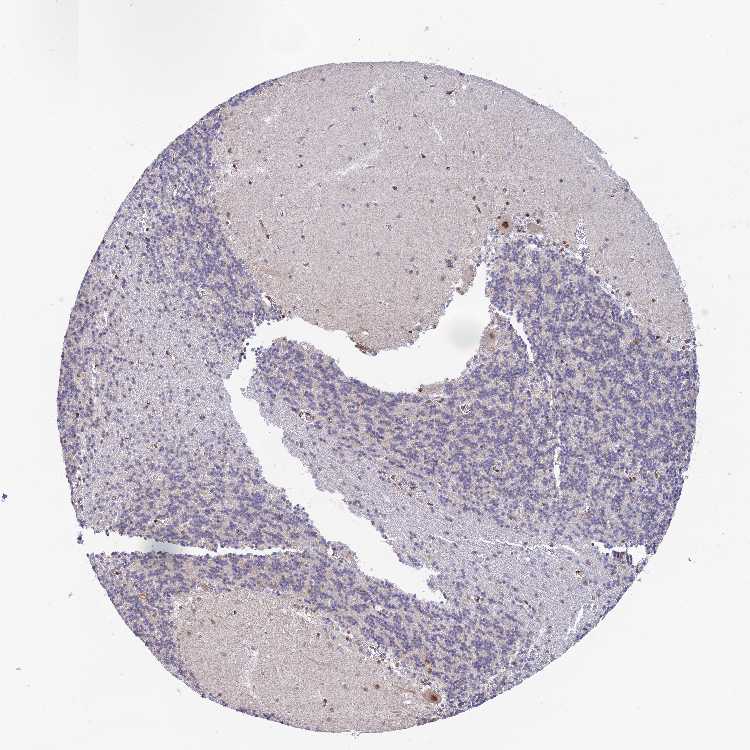

CEREBELLUM - Antibody stainingi

Antibody staining in the annotated cell types in the current human tissue is reported as not detected, low, medium, or high, based on conventional immunohistochemistry profiling in selected tissues. This score is based on the combination of the staining intensity and fraction of stained cells.

Each image is clickable and will lead to virtual microscopy that enables deeper exploration of all samples and also displays staining intensity scores, fraction scores and subcellular localization as well as patient and tissue information for each sample.

Antibody HPA043746

Purkinje cells Medium

Cells in granular layer Not detected

Cells in molecular layer Low